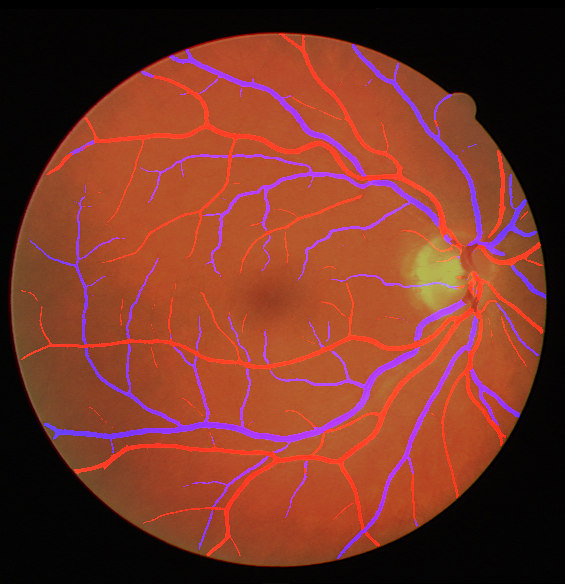

VI-A Retinal Artery and Vein Segmentation

As reported in Table IV, we compared the SegRAVIR model against competing deep learning-based segmentation approaches on the RAVIR dataset. Evidently, SegRAVIR outperforms these methods as judged by all metrics for artery and vein classes with a healthy margin. In terms of Dice score, SegRAVIR outperforms CE-NET, IterNet and AG-Net by , and for artery segmentation and by , and for vein segmentation, respectively. Fig. 4 presents a qualitative comparison of the semantic segmentation outputs of SegRAVIR, CE-Net, and U-Net. Specifically, SegRAVIR yields more accurate vessel topology (i.e., thickness and orientation) segmentation with higher pixel-wise classification accuracy.